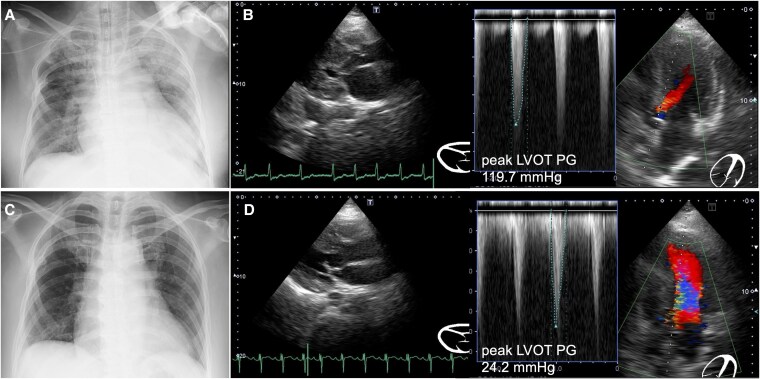

Case summary: A 51-year-old woman was admitted with cerebral haemorrhage and underwent emergency craniotomy. The patient experienced repeated episodes of acute heart failure, leading to several resuscitation attempts and requiring extended MV. Echocardiography revealed severe LVOT obstruction (peak LVOT pressure gradient, 119.7 mmHg). Attempts at volume optimization and pharmacological therapy failed to wean from MV or achieve haemodynamic stability. Given the patient's critical condition, rescue PTSMA was performed, which significantly reduced the LVOT gradient, thereby allowing aggressive volume reduction with haemodialysis and successful extubation within a week.